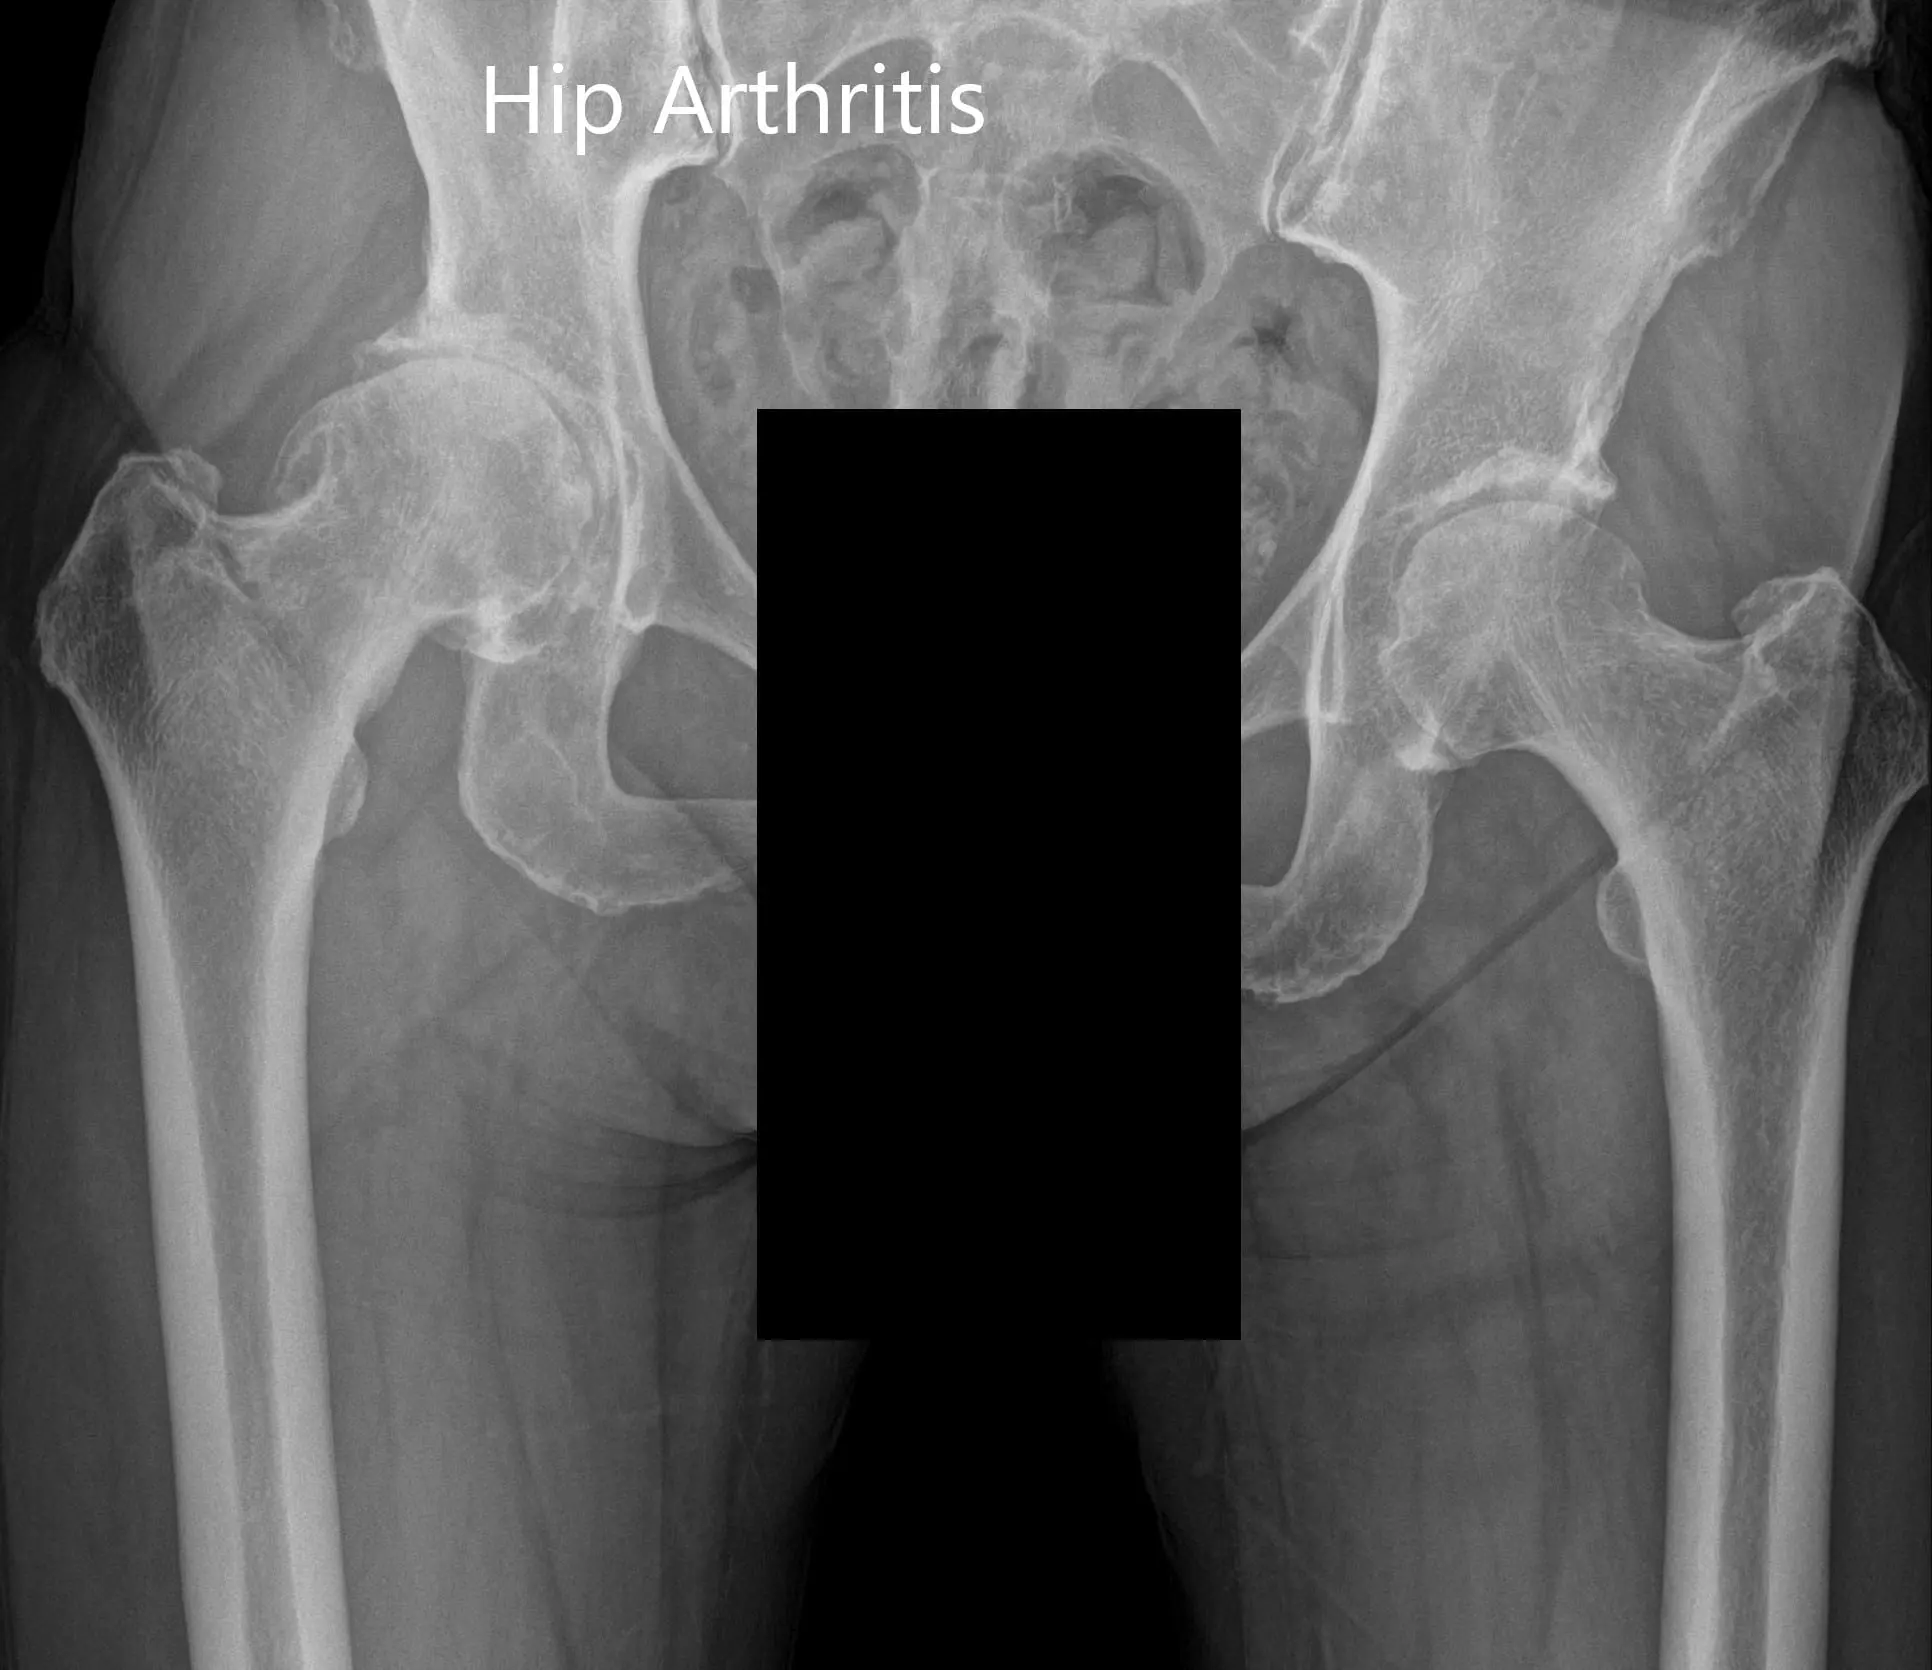

Imaging revealed osteoarthritis of the right hip with joint space reduction and osteophytes. The patient was advised right total hip robotic replacement. The risks, benefits, and alternatives were discussed with the patient at length and she agreed with the plan.

Preoperative X-ray Showing the AP and lateral views of the right hip.

Preoperative X-ray showing the AP view of the pelvis with both hips.